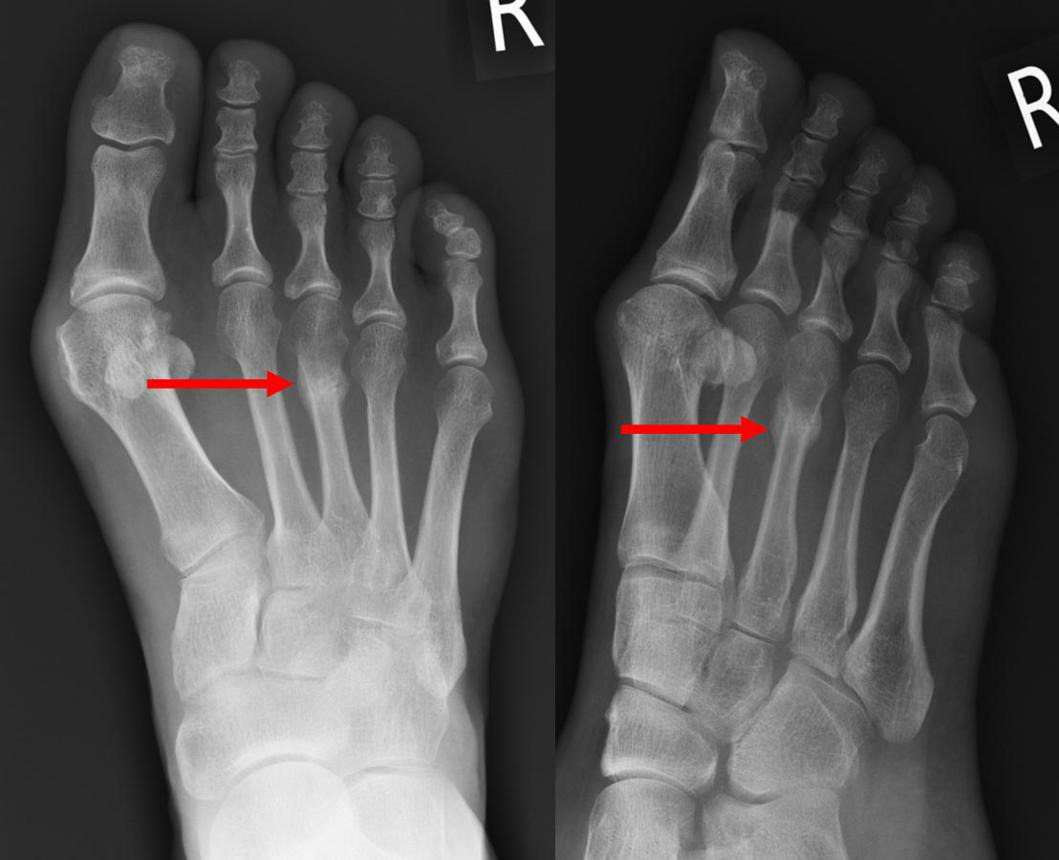

https://adsense.google.com/adsense/u/1/pub-9161951367286286/myads/sites/preview?url=notion6988.tistory.com 🏃‍♂️ 러닝 후 생긴 ‘발등’ 통증… 2주 넘으면 근육통 아닌 ‘이것’